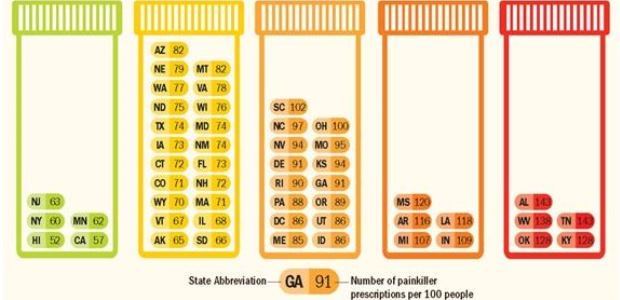

There is no health reason that can explain why health care providers in the highest-prescribing states wrote almost three times as many opioid painkiller prescriptions as their counterparts in the lowest-prescribing state.